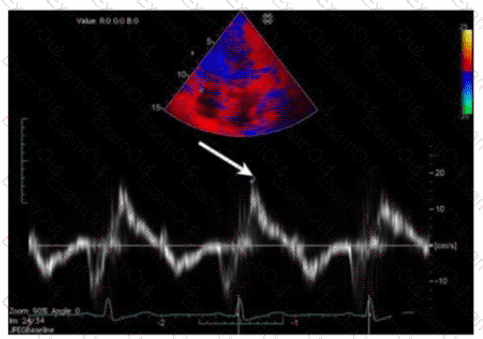

Which measurement is indicated by the arrow on this image?